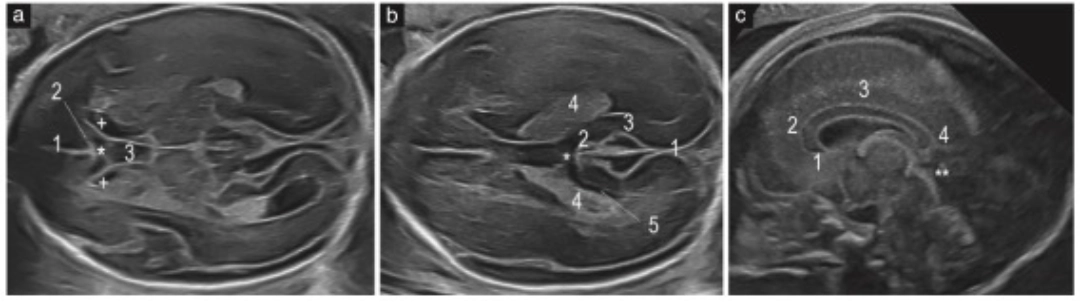

Caso de pACC a las 23 semanas. Aparentemente, el CSP tiene forma normal (índice ≥1.5), pero la imagen sagital muestra ausencia del rostrum y parte del esplenio del cuerpo calloso. La evaluación del complejo posterior fue clave para sospechar la anomalía. Fuente: Viñals et al., 2025.

Estos hallazgos son visibles en el examen ecográfico estándar del segundo trimestre.